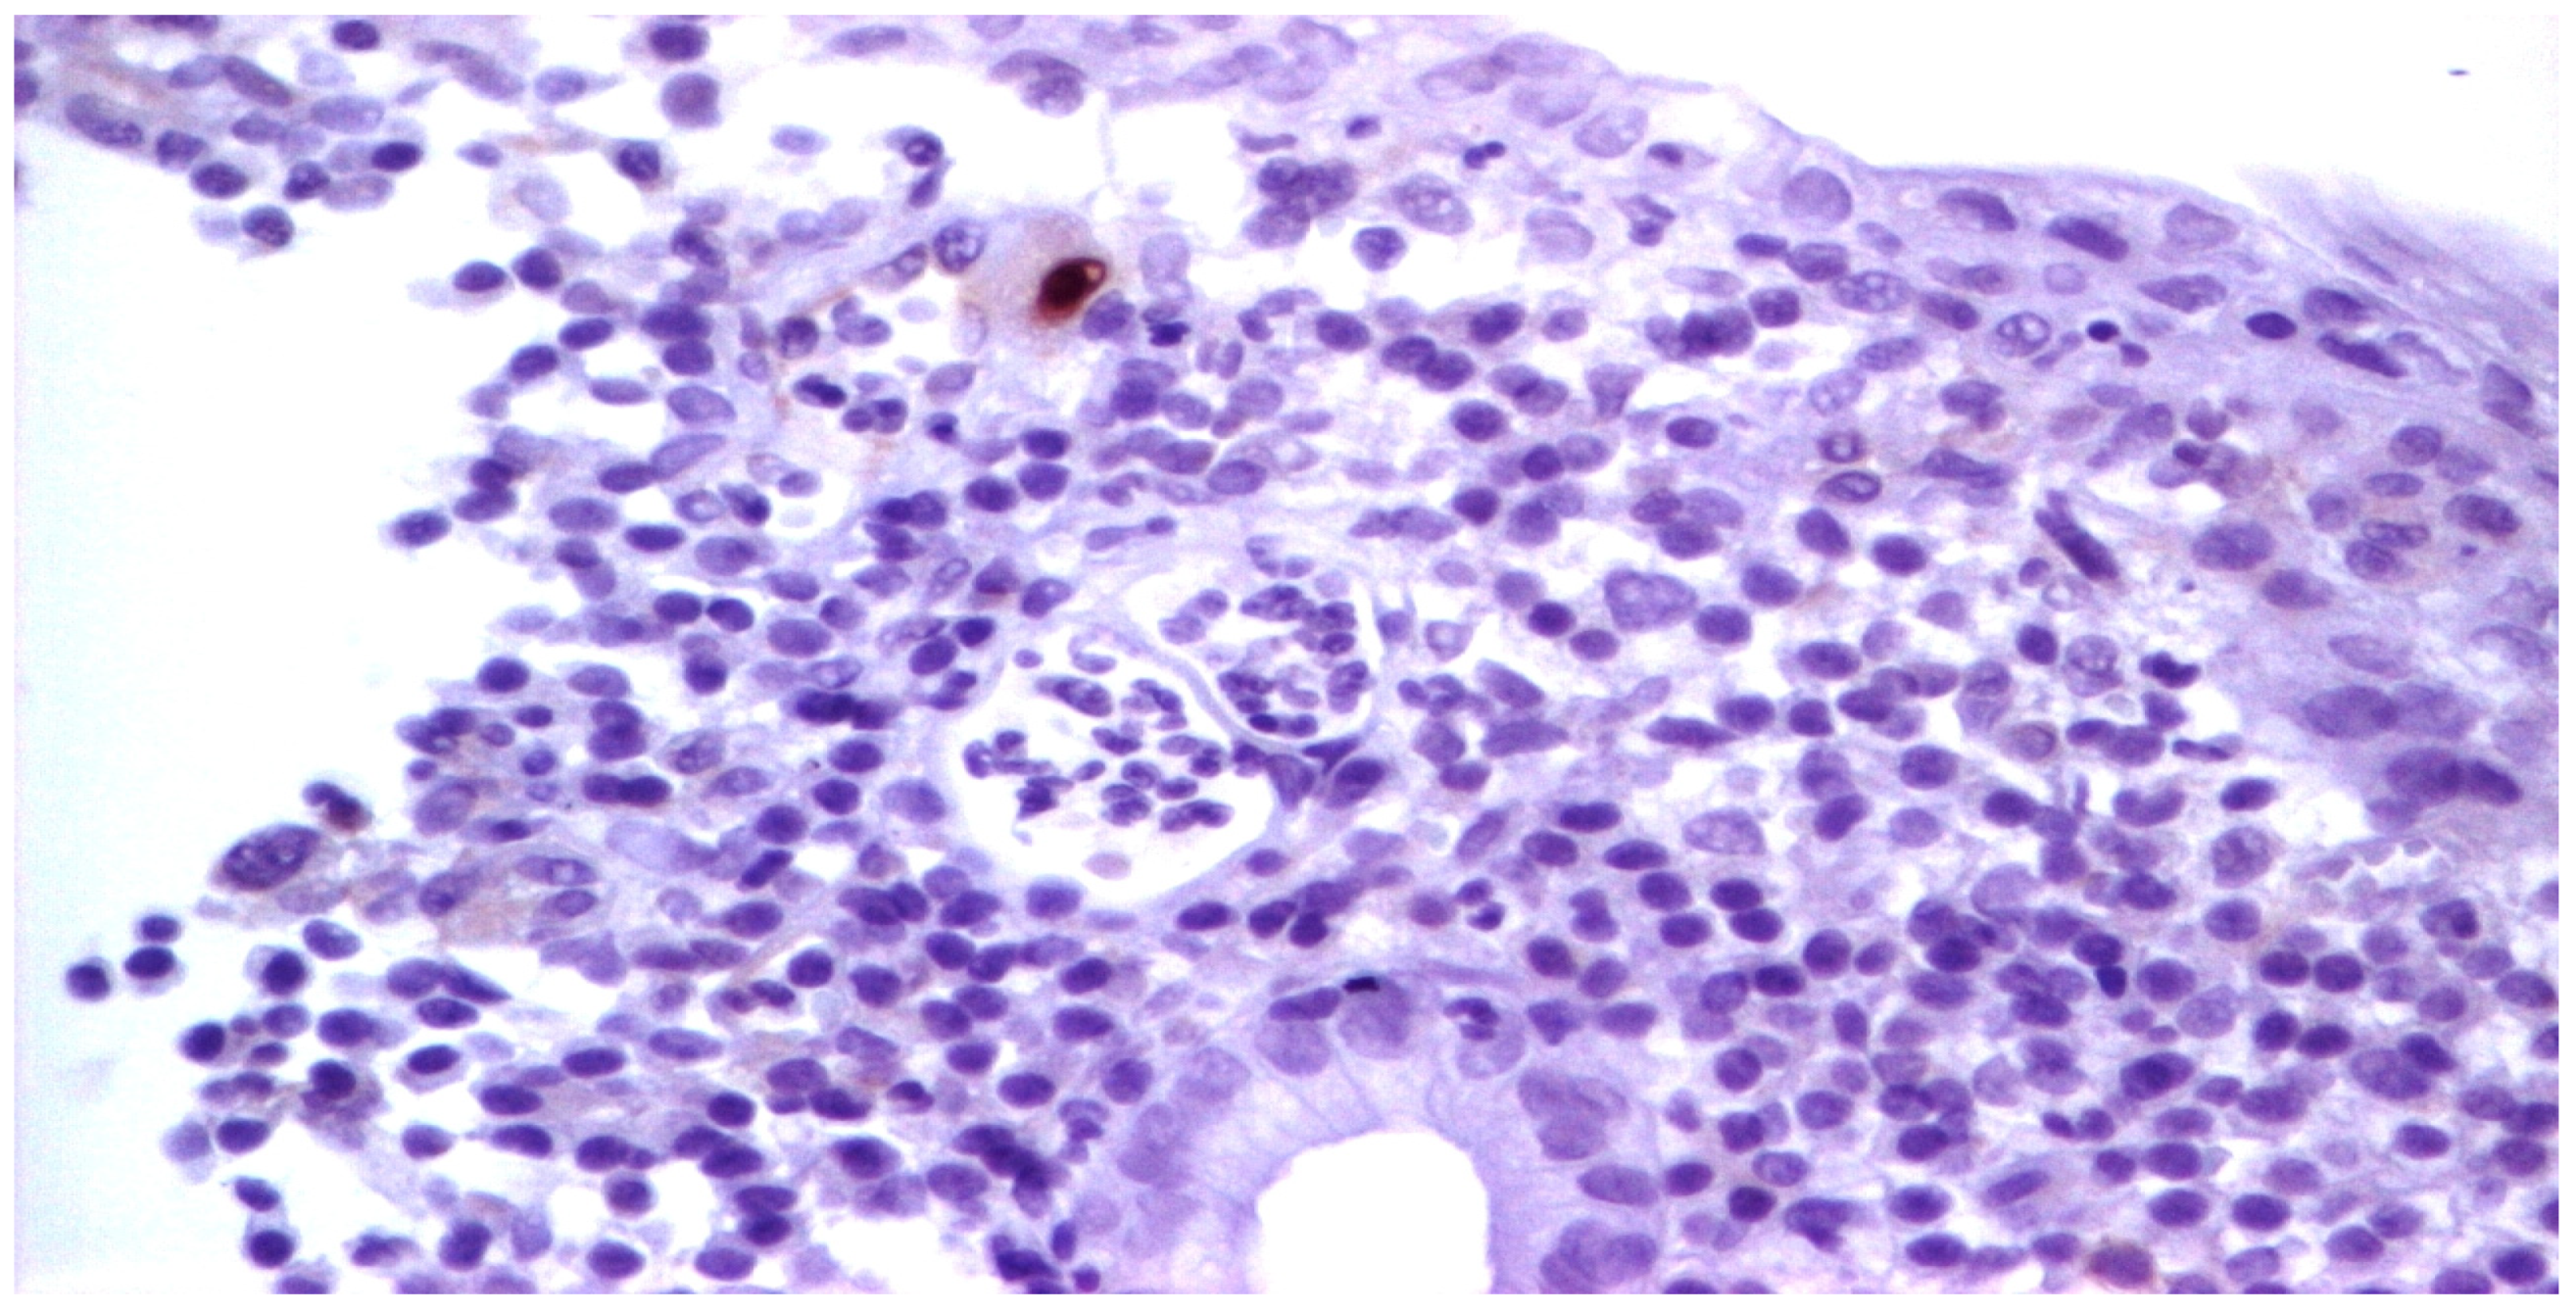

Figure 8.

We identified isolated endothelial cells with viral inclusions in the granulation tissue (Hematoxylin eosin staining, ×40).

Upon admission, laboratory tests revealed leukopenia, mild hypochromic normocytic anemia, thrombocytopenia, and signs of inflammation, cholestasis, and hepatocellular injury hepatic cytolysis syndrome. To determine the cause of the acute episode, we performed bacterial and mycological stool tests, as well as serological viral marker testing. We found an increase in HCMV IgG levels compared to the value at the initiation of biological therapy: 148 AU/mL and, later, 500 AU/mL. The plasma HCMV DNA was 7320 UI/mL. The HBs Antigen and HCV Antibody tests were negative. The value of anti-adalimumab antibodies was 0.5 (<10 AU/mL). Due to the biochemical changes in the liver, sclerosing cholangitis was initially suspected. However, this was ruled out with the aid of a cholangioMRI and negative pANCA values. Given these findings, HCMV hepatitis was suspected, and an ileocolonoscopy was performed. The endoscopic appearance was not characteristic of HCMV colitis, as there were erosions, ulcerations, a disappearance of the vascular pattern, and mucosal friability, the aspect being circumferential up to the level of the terminal ileum, corresponding to Mayo 8 points (Figure 7). Serial biopsies were collected, especially from the left side. Histopathological examination revealed a destructive pattern with chronic architectural changes and abundant chronic inflammation, including basal plasmocytosis and marked activity with crypt abscesses observed in all biopsy fragments. Rare HCVM viral inclusions were identified on HE staining at the level of the endothelial cells in the capillaries. The presence of the viral inclusions was confirmed by immunohistochemistry (Figure 8 and Figure 9). During hospitalization, the patient was treated with electrolyte solutions, and systemic therapy with intravenous ganciclovir was initiated at 5 mg/kg every 12 h for 3 days, followed by oral valganciglovir at a dose of 900 mg twice a day for 21 days. Additionally, the patient received Mesalazine at a dose of 3 g/day, and hepatoprotective measures were also continued, along with Adalimumab.